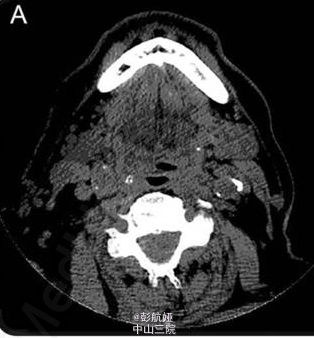

头颅血管造影(CTA)结果(如图 1 所示)示颈椎管可见斑点征和高密度影。 进一步完善 MRI 证实为 C4-T1 的硬膜外血肿(如图 2 所示)